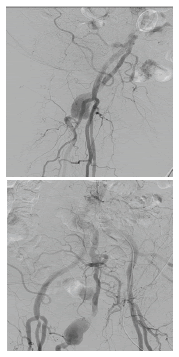

En la arteriografía (figura 1) se evidenció: una arteria ciática persistente derecha permeable, con degeneración aneurismática proximal, con recorrido por el muslo sin lesiones y unión con la arteria poplítea en su segunda porción; trombos suboclusivos en dicho aneurisma; ateromatosis de la arteria femoral superficial derecha en su tercio medio y distal, con estenosis crítica en su unión con la arteria poplítea, y llegada distal a este sitio de la arteria ciática persistente. Las arterias ilíacas y femorales izquierdas fueron normales. Se observaron trombos oclusivos en la arteria femoral superficial derecha distal, en la primera porción de la arteria poplítea, y en las arterias tibial posterior y peronea.